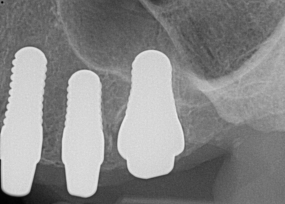

Fig 8. Preoperative periapical radiograph.

Figure 8

Fig 9. 12-week postoperative periapical radiograph.

Figure 9

Essentially, after integration and evaluation of soft tissue at 12 to 16 weeks subsequent to surgical placement of the ceramic implant, the implant is treated similarly to a natural tooth receiving a long-term restoration, and the protocol is the doctor's choice for soft-tissue management at the time of the final impression. Radiographic examination in Figure 8 and Figure 9 revealed that bone volume and soft tissue were preserved, primarily due to exceptional biocompatibility and the PRF biologics implemented after the atraumatic extractions.